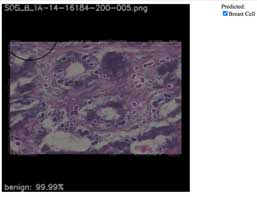

Breast cancer cell

(H&E stained specimen)

- Highlight breast cell location

- Classification